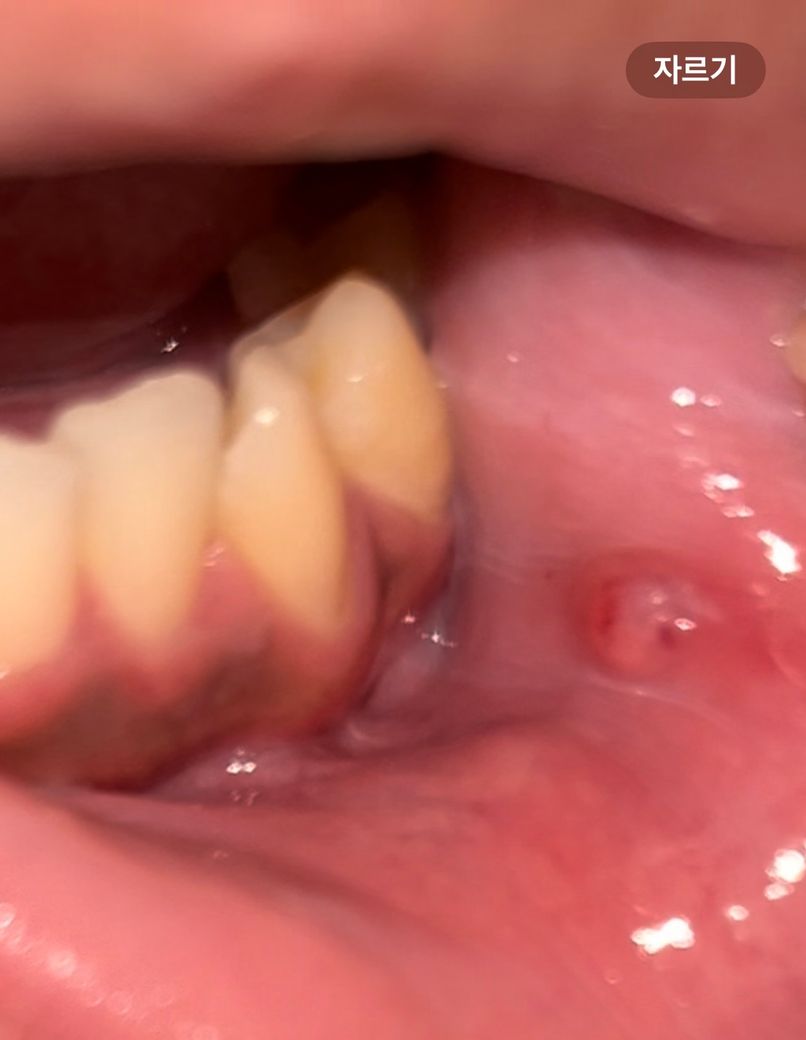

구강암 같은 건가요 혹시 몰라 불안해서 여쭤봅니다

6~10일 정도 된 거 같고 처음엔 완전 구내염처럼 생겼는데 생김새가 바뀌어서 당황스럽네요

흡연자입니다ㅜ

• 1번 째 사진

구강암이 이니기에 걱정하지 않아도 되며, 해당부위 소독을 위해 헥사메딘 가글액 사용이 증상경감에 도움이 됩니다. 흡연을 하는 것은 회복을 더디게 할수 있습니다.

잇몸을 잘 못 씹어서 생긴 물집일 가능성이 높아보이며 크기가 더 커지거나 사라지지 않으면 치과 가보시는 게 좋겠습니다.

잇몸에 물집이 생긴거 같습니다. 큰문제가 잇는건 아니니 터트리면 괜찮아 지실꺼니 너무 걱정하지마세요.

구내염애 있는 부위가 계속해서 자극이 되면 해당부위가 커질수 있습니다.